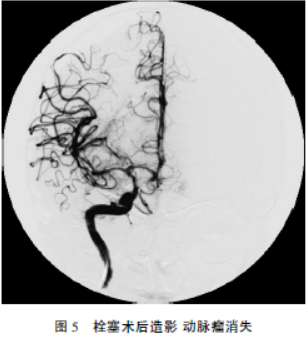

介入栓塞治疗肺吸虫感染性颅内动脉瘤一例

病史摘要:27岁男性患者,主诉“反复发热、咳嗽、咯痰3个月伴突发头痛3d”。既往半年前有生吃溪蟹史。诊疗过程:入院查体意识清楚,无皮下结节,双下肺叩诊浊音,颈强直。急诊头部CT示蛛网膜下腔出血。住院后全脑DSA示右侧大脑中动脉末端动脉瘤;胸部CT示双肺感染等;实验室检查血清肺吸虫IgG抗体阳性,血常规嗜酸性粒细胞比例升高等。诊断为感染性颅内动脉瘤肺吸虫病。行右侧大脑中动脉M4段动脉